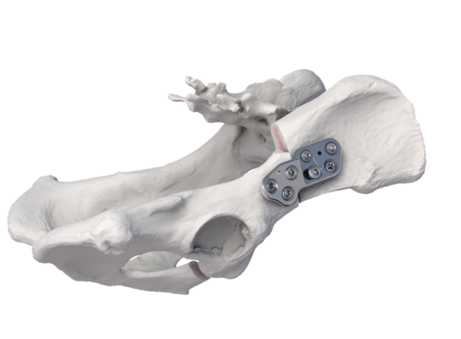

3. Was ist ein totaler Hüftgelenkersatz?

Bereits seit 1974 gibt es dieses vielfach erprobte und standardisierte Verfahren, bei dem ein fehlentwickeltes- oder stark geschädigtes Gelenk ersetzt wird. Alle Anteile des Gelenks werden hierbei durch synthetische/künstliche Materialen ersetzt. Dazu gehören die Beckenpfanne, der Oberschenkelkopf und der Oberschenkelhals. Aufgrund einer großen Vielfalt von anatomischen Gegebenheiten bei unseren tierischen Patienten, gibt es sehr unterschiedliche Implantattypen von denen manche in den Knochen geschraubt-, gehämmert oder einzementiert werden. Der Implantattyp wird bei der Voruntersuchung in jedem Fall einzeln festgelegt, um ein optimales Ergebnis zu erzielen.